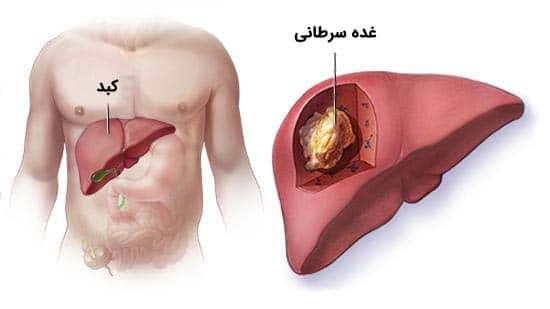

قیمت: 52٬000 تومان - دسته بندی فایل: پاورپوینتپاورپوینت سرطان کبد

فروش ویژه پاور پوینت حرفه ای سرطان کبد با تخفیف استثنایی فقط 32 هزار تومان تعداد اسلاید: 27 اسلاید